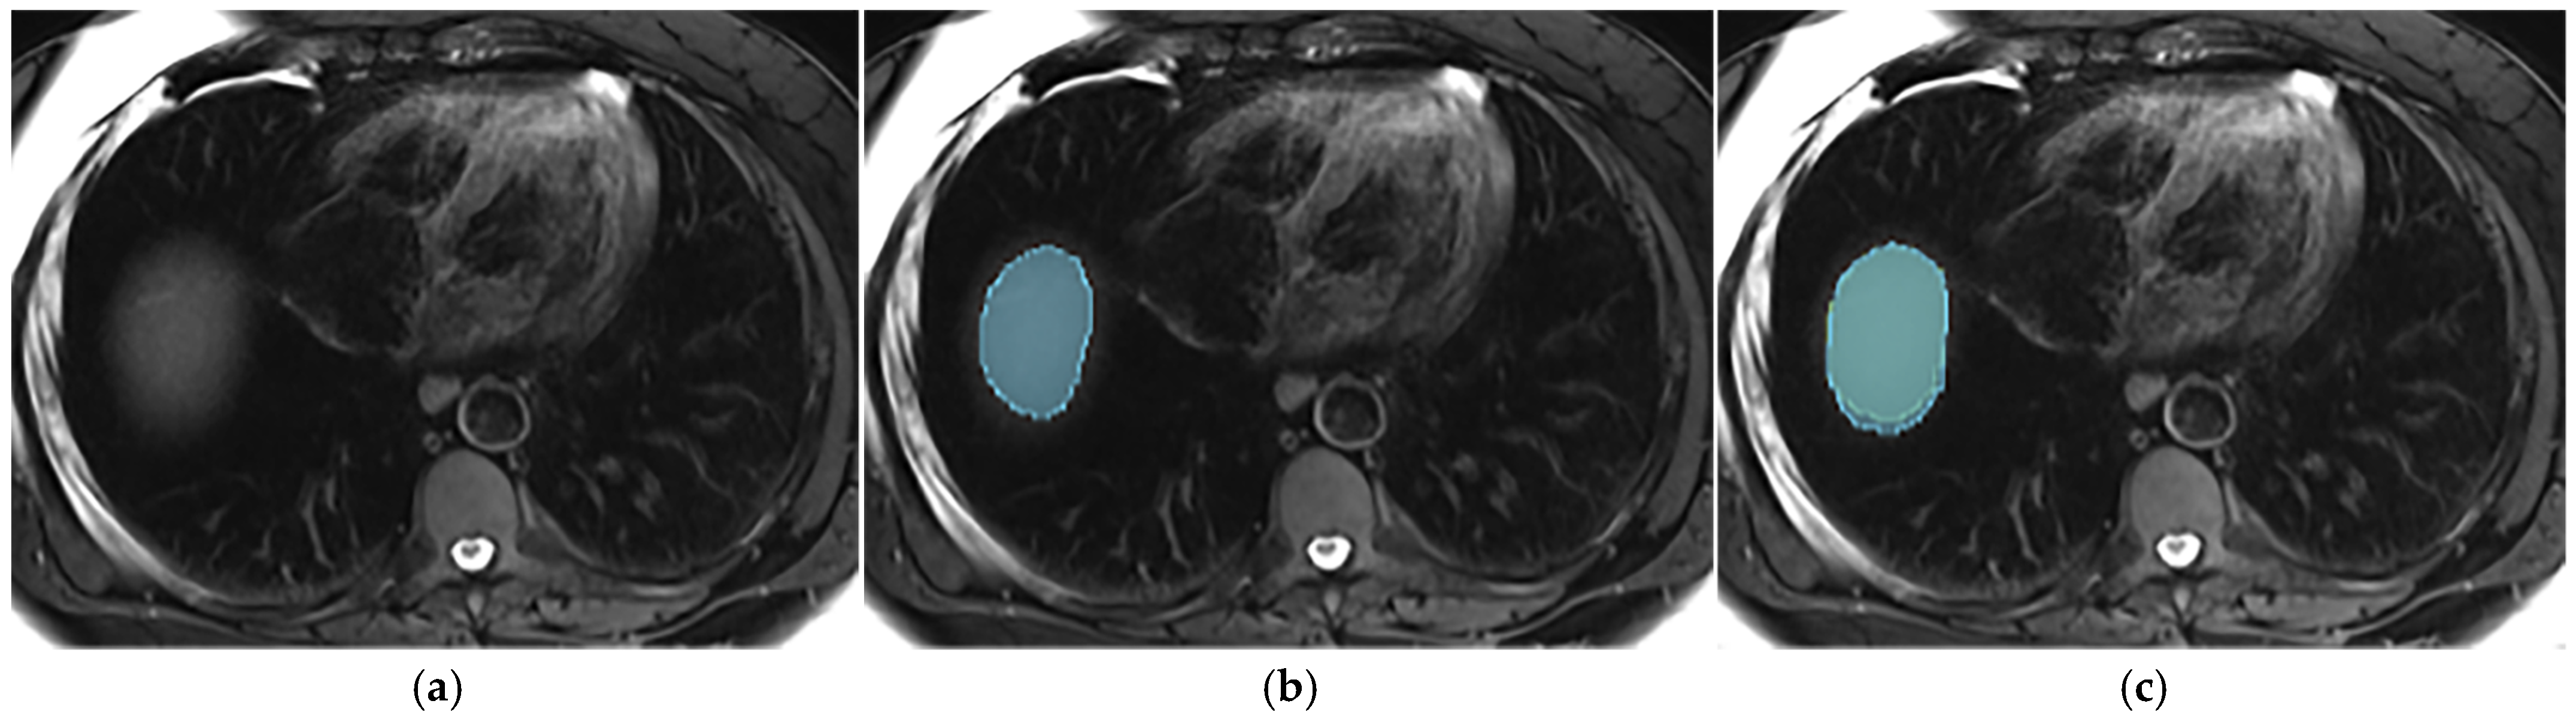

Appendix A.5. Multi-Part Liver Parenchyma

Appendix A.6. Presence of Respiratory Artifacts